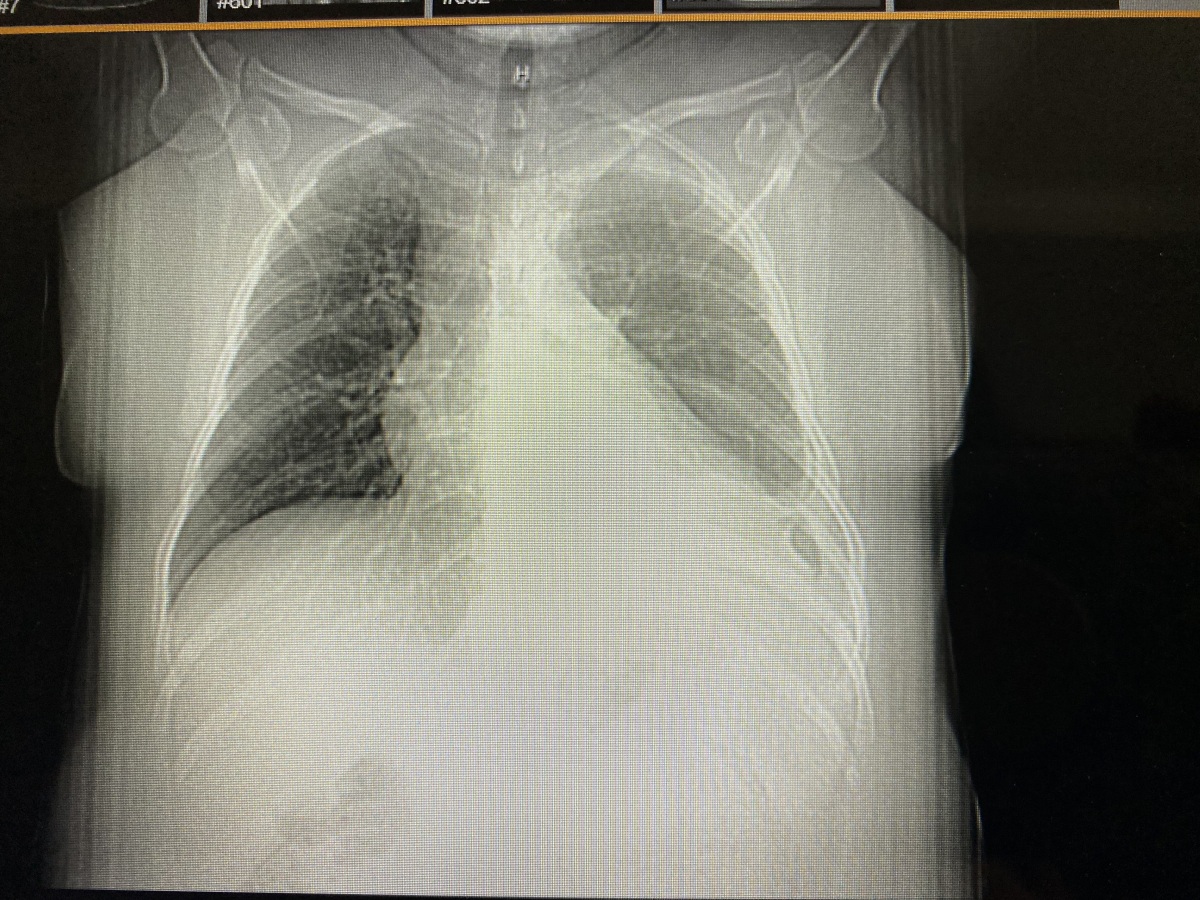

Diagnosed with Stage IV ALK (Anaplastic Lymphoma Kinase) positive Non-Small Cell Lung Cancer at 41 came as a shock.  I sought medical attention after experiencing periods of shortness of breath and coughing during activity. Due to my persistence and that of my doctors, I soon found that my shortness of breath was much more than a nuisance, but rather cancer that had metastasized throughout my body causing havoc on my lungs.

It has been four years and counting since my diagnosis and I am currently in remission. I credit my current good health to the diligence of my oncologists staying up to date on this rare form of lung cancer.  I believe receiving a biomarker test (an analysis of the tissue/blood) during my initial diagnosis was crucial as it revealed I had a rare gene mutation that was driving my cancer, giving me more options for the best course of treatment.